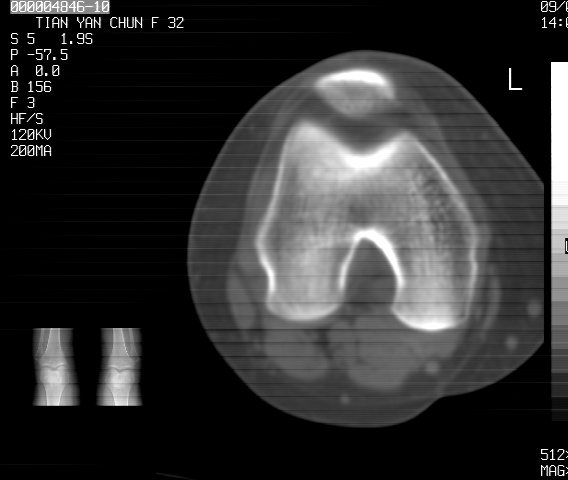

标题: CT18487:请会诊,女32岁,左膝疼痛数日 [打印本页]

标题: CT18487:请会诊,女32岁,左膝疼痛数日

关节面软骨有硬化环考虑退行性变

定位片可见髁间棘骨质增生,支持膝关节退行性变。

定位片可见髁间棘骨质增生,支持膝关节退行性变。建议mri 检查

考虑骨性关节炎